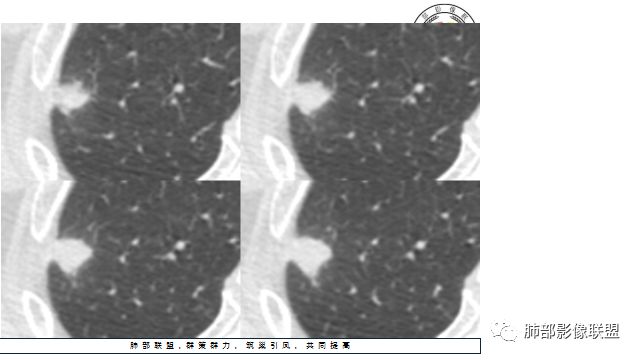

胸CT:右上肺结节,病灶位于胸膜下,边缘可见平直 u型征 软毛刺 晕,增强可见延迟强化,病灶中心低密度区。

4.增强扫描成明显环形强化,中央液化坏死,内壁清楚且较为规整。

分析:

1.肺鳞癌是容易坏死,但如此小的结节出现影像明显可见的坏死区,且内壁如此清楚规整,我们临床实践中肿瘤非常少见,重要的事情说三遍!!!

病灶缺乏典型的分叶且明显可见的坏死区,腺癌就更为罕见。

2.病灶周边可见薄晕,会想到隐球菌感染,可以出现空洞,但内壁如此清楚的空洞少见。